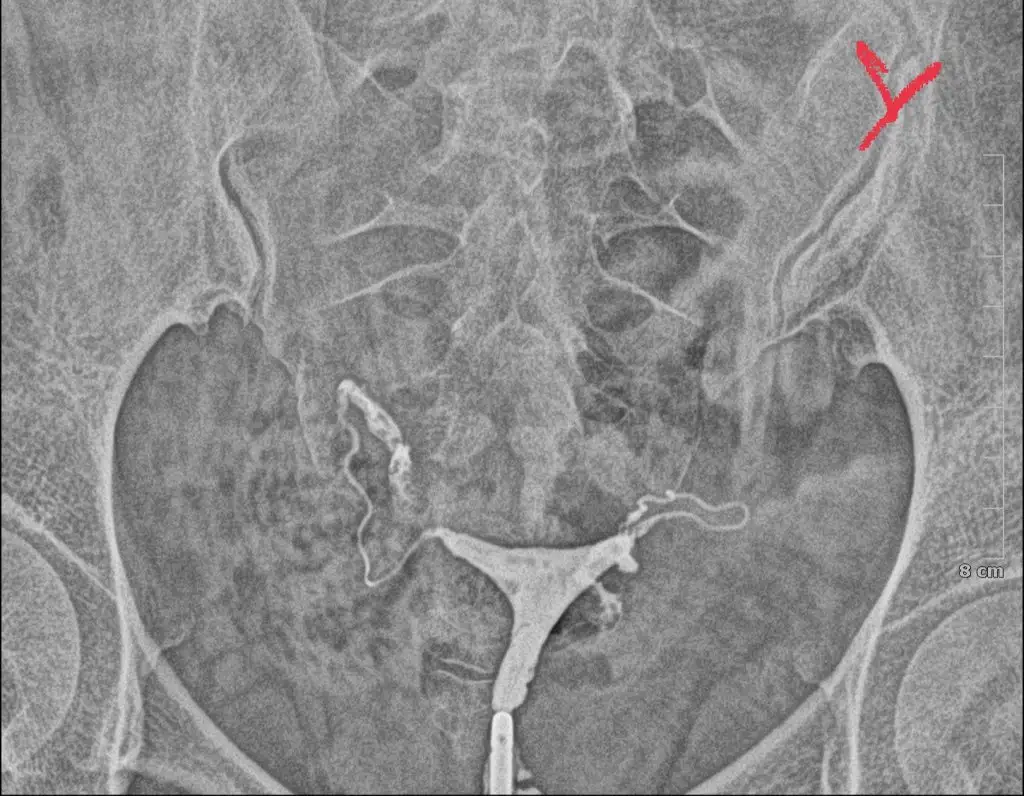

Filmi çektirdiğiniz yerde doktora yorumlatsaydınız.Yardımcı olabilecek var mı